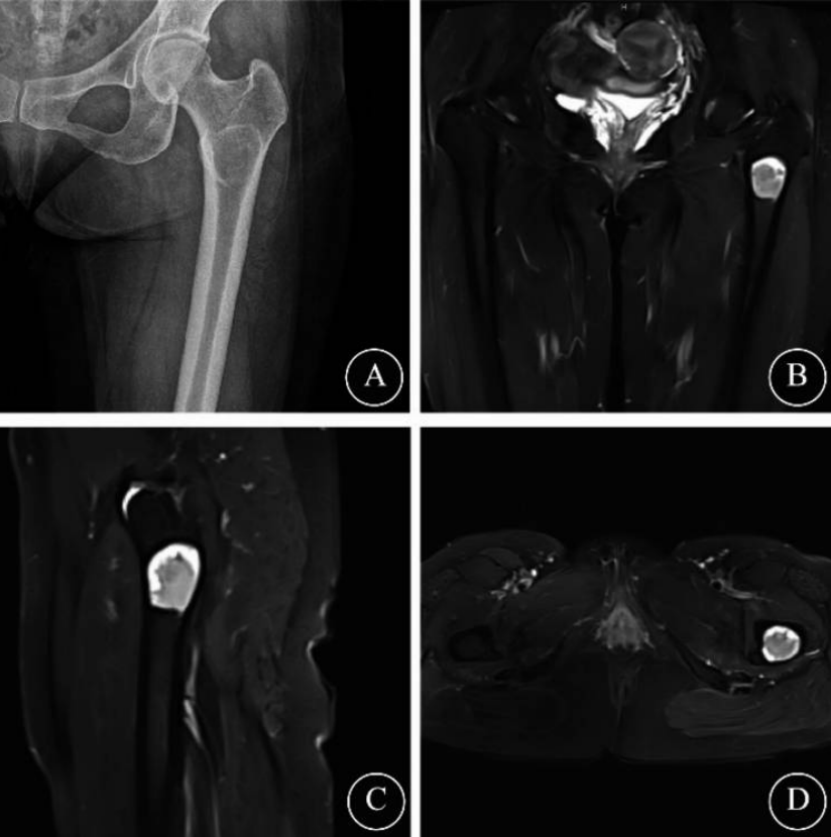

女性,10岁,患者诉右股骨肿瘤切除术后11个月,右大腿疼痛复发1月余。患者11个月前因右髋持续性疼痛行右股骨肿瘤开放切除、植骨融合术,术后疼痛缓解。近1月出现右大腿间歇性刺痛,夜间加重,口服非甾体抗炎药可缓解。影像学检查提示右股骨颈复发性骨样骨瘤。考虑患者肿瘤复发且年龄小再行开放手术损伤大,于是广西医科大学第一附属医院脊柱骨病外科团队采用AUNES技术行单通道肿瘤切除+同种异体骨移植。手术切口仅4cm,术中仅一次C臂透视定位,内窥镜下使用高速钻和射频电极进行病灶刮除,术野清晰,操作精准。术后第一天拔除引流管,第三天开始康复训练。术后一周疼痛评分降至2分,一个月随访时疼痛完全消失,切口愈合良好,无神经功能异常,影像学显示植骨位置良好,无复发迹象。

图4 骨样骨瘤复发患者影像